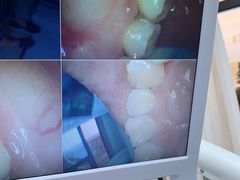

• 牙博士口腔(杨浦店)

• -牙博士口腔(杨浦店)

微笑也神烦 | 20-07-31